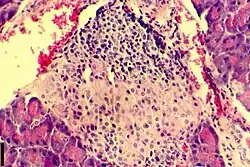

| A histological image of an inflammatory infiltration of the islets of Langerhans of the pancreas | |

Insulitis is an inflammation of the islets of Langerhans, a collection of endocrine tissue located in the pancreas that helps regulate glucose levels, and is classified by specific targeting of immune cell (T and B lymphocytes, macrophages and dendritic cells) infiltration in the islets of Langerhans.[4][5][6][7] This immune cell infiltration can result in the destruction of insulin-producing beta cells of the islets, which plays a major role in the pathogenesis, the disease development, of type 1 and type 2 diabetes. Insulitis is present in 19% of individuals with type 1 diabetes and 28% of individuals with type 2 diabetes.[1][8][9] It is known that genetic and environmental factors contribute to insulitis initiation, however, the exact process that causes it is unknown.[10] Insulitis is often studied using the non-obese diabetic (NOD) mouse model of type 1 diabetes. The chemokine family of proteins may play a key role in promoting leukocytic infiltration into the pancreas prior to pancreatic beta-cell destruction.[11]